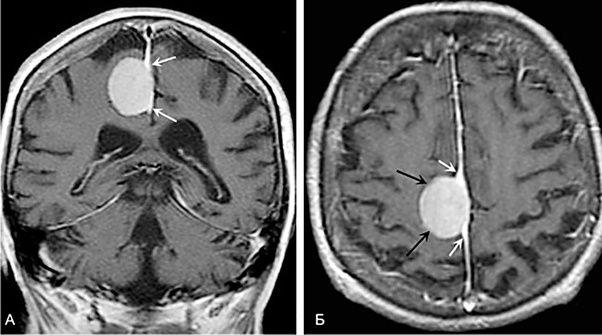

Жалобы с которыми пациенты обращаются за медицинской помощью зависят от локализации опухоли (менингиомы основания черепа, менингиомы задней черепной ямки, конвекситальные менингиомы, внутримозговые опухоли, опухоли желудочков головного мозга).

В плане предоперационного обследования и контроля за пациентом в послеоперационном периоде проводится МСКТ и МРТ томография головного мозга, лабораторное и нейрофизиологическое обследование, что позволяет избежать возможных осложнений связанных с удалением опухолей головного мозга.